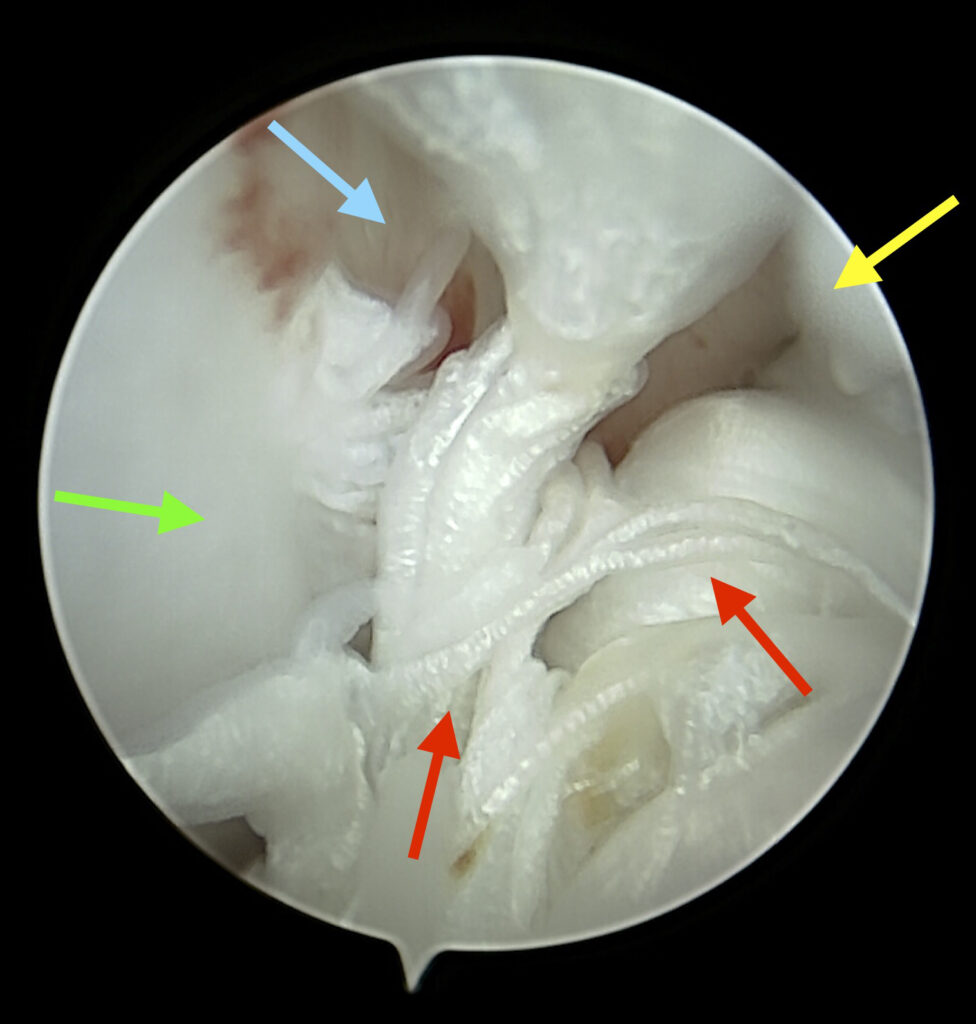

• Arthroscopie pour nettoyer une articulation

Exemple d’athroscopie